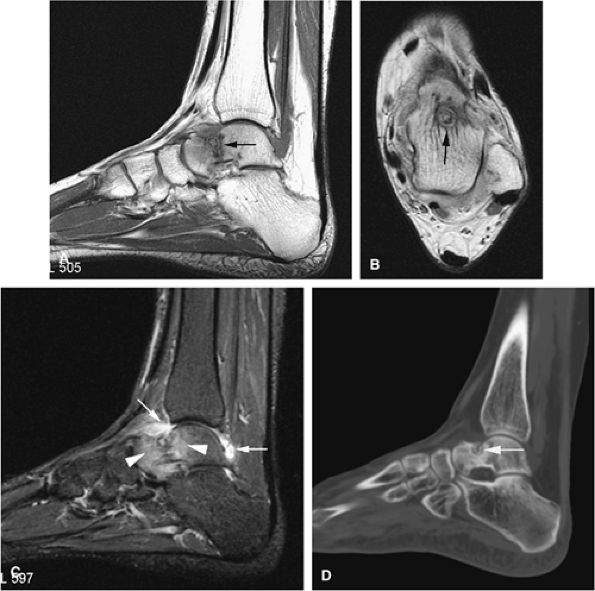

![]() |

FIGURE 14-9 ● Sagittal (A) and axial (B) T1-weighted images show subcortical osteoid osteoma with a low-signal-intensity nidus (arrow) of the talar neck. (C) Corresponding sagittal fat-suppressed T2-weighted fast spin-echo image demonstrates surrounding hyperintense bone marrow edema (arrowheads). A joint effusion and synovitis is present (arrows). (D) Sagittal CT image demonstrates the osteoid osteoma nidus in the talar neck (arrow).